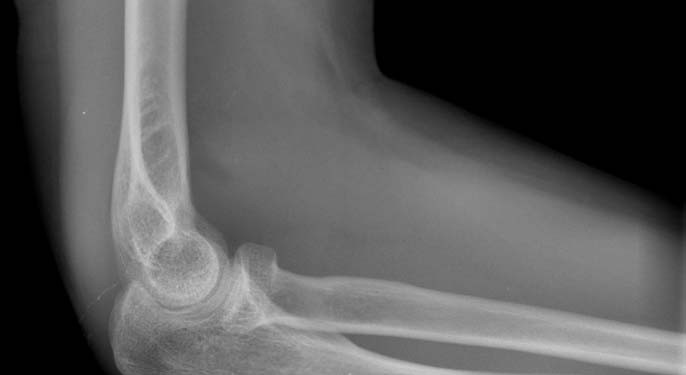

Dirsek Çıkığı Redüksiyonu

Dirsek Çıkığı – Redüksiyonu